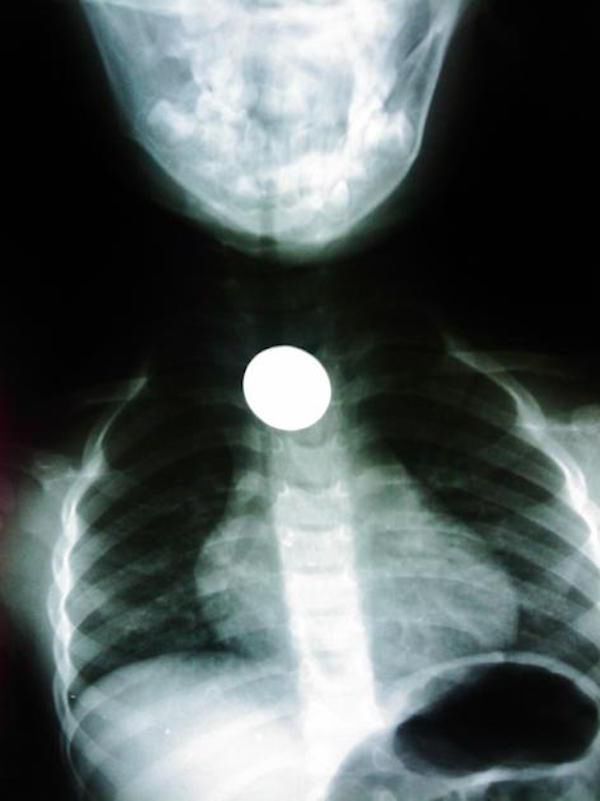

/ 15Moneta

Jak już miał apetyt na pieniądze, to mógł postawić na banknoty. Podobno się lepiej trawią.